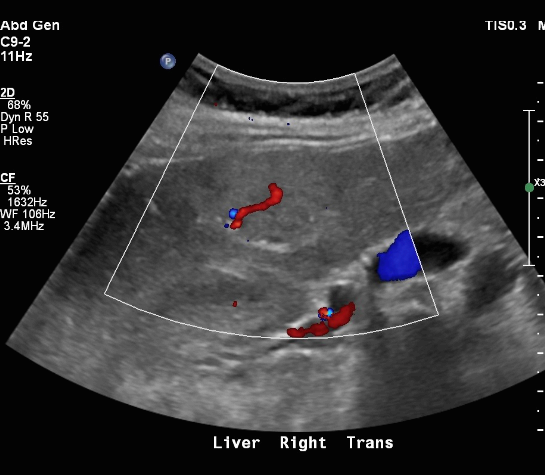

FNH (Focal Nodular hyperplasia) US finding

- isoechoic lesion

- central feeding artery